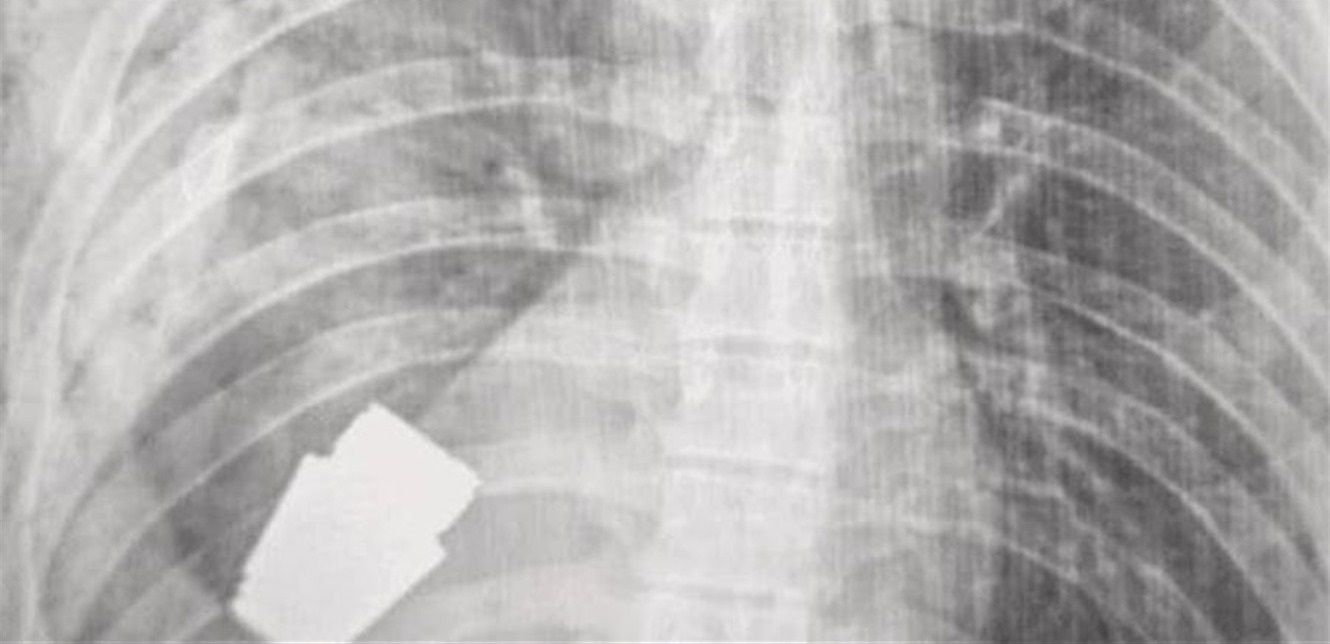

وأكد حاكم المنطقة، سيرهي بورزوف، في منشور على "فيسبوك" أمس أن "أطبائنا العسكريين أجروا عملية لإزالة قنبلة غير منفجرة من جسد جندي".

ومع ذلك، قال بورزوف إن الدكتور فيربا كان قادراً على إجراء الجراحة بنجاح وإزالة القنبلة اليدوية، مضيفاً أن "التدخل العملياتي كان ناجحاً وتم إرسال الجندي المصاب لإعادة التأهيل والتعافي".